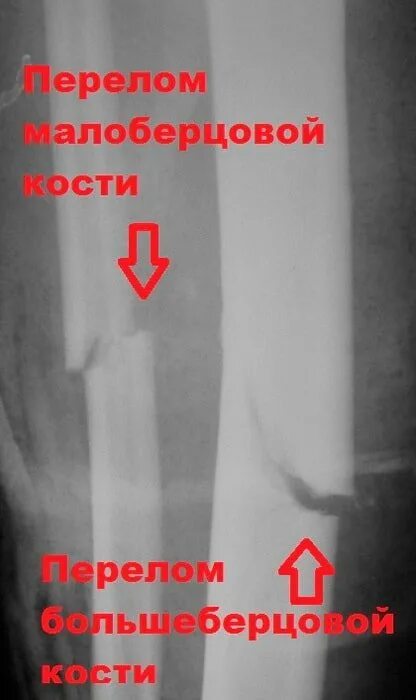

Сколько срастается малая берцовая